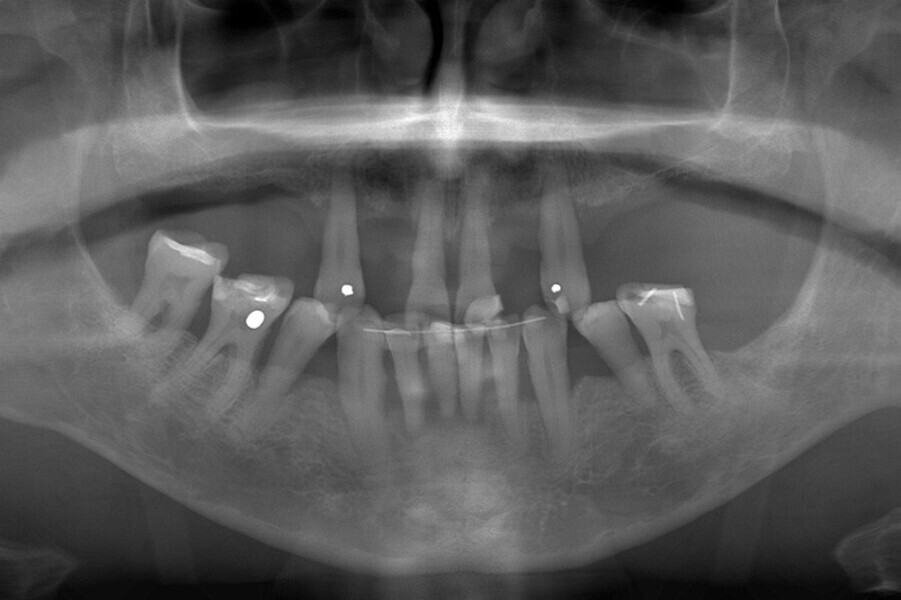

Fig. 21. Rx Pre-operatoria, Prótesis híbrida inmediata con 5 años de evolución y Rx Control a los 5 años.

Fig. 22. Rx Pre-operatoria, Prótesis híbrida inmediata con 5 años de evolución y Rx Control a los 5 años.

Fig. 23. Rx Pre-operatoria, Prótesis híbrida inmediata con 5 años de evolución y Rx Control a los 5 años.